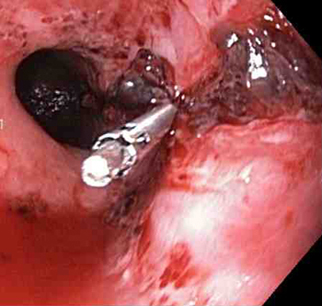

A mechanical method (e.g., clips) with or without adrenaline (epinephrine). In practice, both through-the-scope clips (TTSC) and over-the-scope clips are options depending on availability and expertise. However, for MWT, TTSC usually suffice.[Figure caption and citation for the preceding image starts]: Mallory Weiss tear after application of through-the-scope clip results in haemostasisFrom the personal collection of Douglas Adler; used with permission [Citation ends].

Through-the-scope clips (TTSC), alone or in combination with adrenaline injection to clear the visual field

TTSC are widely available, have a robust evidence base and are usually sufficient to control bleeding in MWT.

TTSC use is as safe and effective as other methods for controlling actively bleeding lesions.[76][77][78][Figure caption and citation for the preceding image starts]: Mallory Weiss tear after application of through-the-scope clip results in haemostasisFrom the personal collection of Douglas Adler; used with permission [Citation ends].